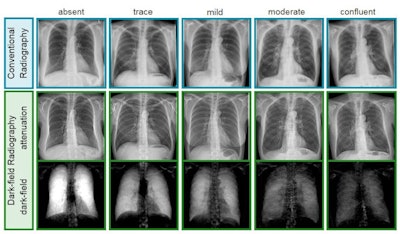

Exemplary radiographs and dark-field chest x-ray images from the study. Image courtesy of Theresa Urban.Dark-field images showed a distinct decrease of signal strength with emphysema severity, as alveoli are denser in these patients, according to the findings. Readers were significantly better able to identify emphysema with images from the dark-field prototype, achieving an area under the curve (AUC) of 0.85 (p < 0.05) compared with conventional images (AUC, 0.74).

In addition, while ratings of adjacent emphysema severity groups with conventional radiographs were only different for trace and mild emphysema, ratings based on images from the dark-field prototype were different for trace and mild, mild and moderate, and moderate and confluent emphysema.